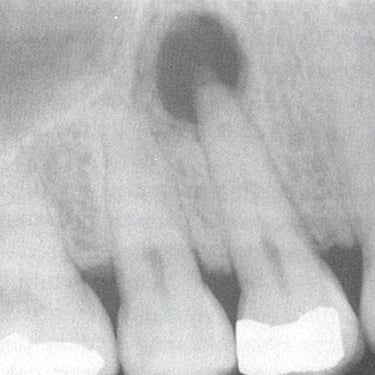

Quiste Periapical

Un quiste periapical es una cavidad llena de líquido en la punta de la raíz del diente, generalmente resultado de una infección crónica.

Los pacientes pueden notar una hinchazón sin dolor en la encía.

El tratamiento incluye el tratamiento de conducto y, a veces, la extirpación quirúrgica del quiste. Si no se trata, el quiste puede crecer y causar complicaciones.